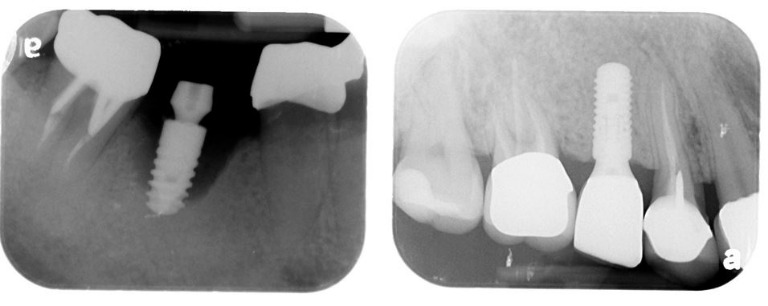

左圖為:沒有定期回診追蹤, 10年後植體周圍炎造成齒槽骨嚴重破壞,植體開始搖動。右圖為:每半年定期回診, 植體周圍組織及骨高度健康穩定。(圖片來源/新光醫訊提供)